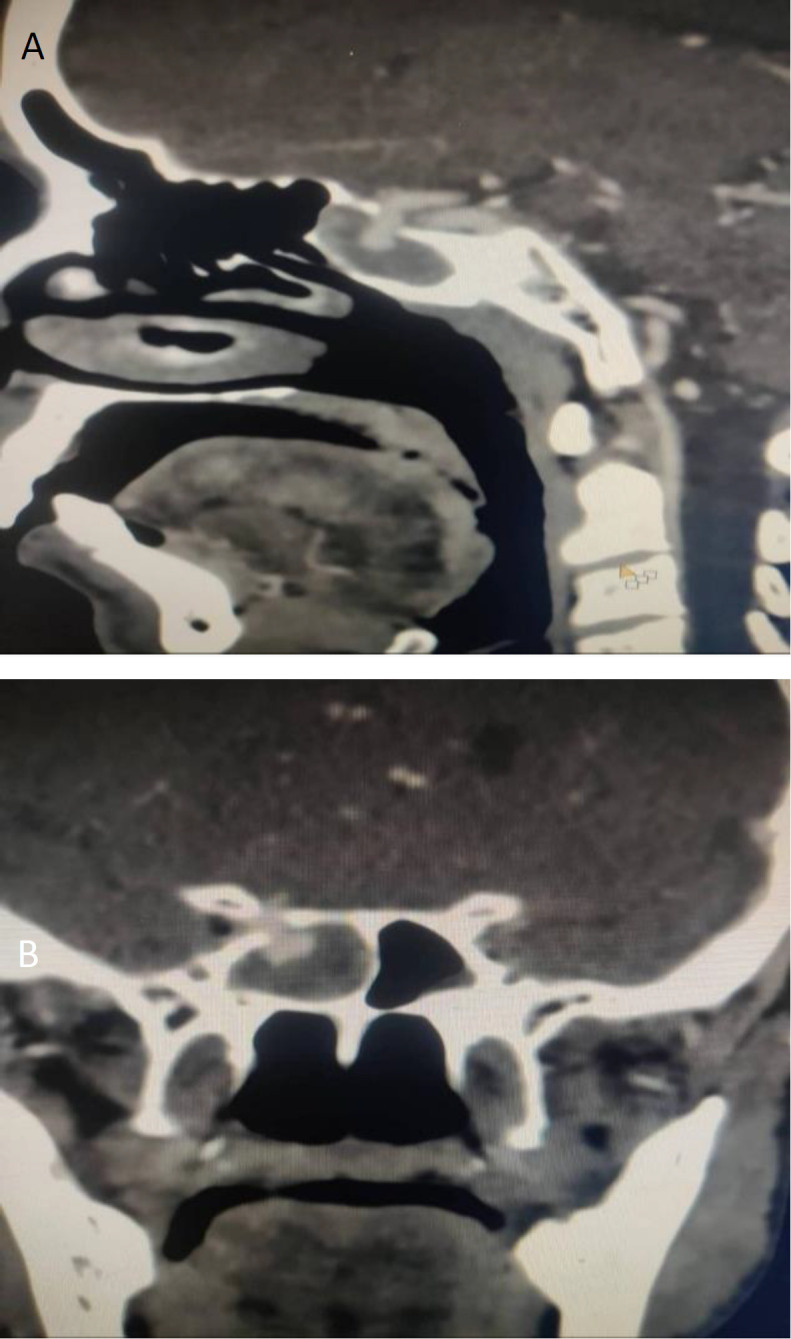

Case report: We report a case of a 57- year old male presenting with recurrent episodes of epistaxis. Contrast-enhanced Computed Tomography of the Paranasal Sinuses and Magnetic Resonance Imaging were performed, which showed a focal defect in the posterolateral wall of the sphenoid sinus through which an aneurysm from the cavernous segment of the Internal Carotid artery was seen herniating into the sinus with an associated hematoma.